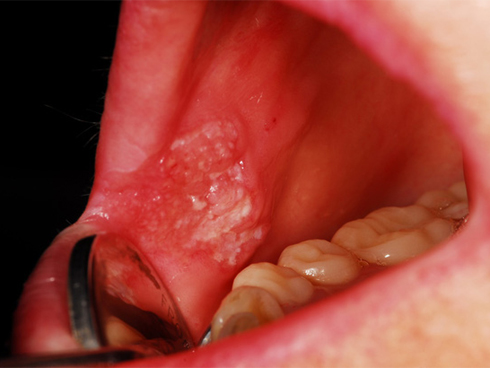

5. Cảm thấy ứ nghẹn, tắc khi nuốt

Nếu bạn thường xuyên cảm thấy thức ăn bị kẹt trong cổ họng hoặc thấy mình thay đổi cách ăn (như cắn miếng bé hoặc tránh những thức ăn lớn), đây có thể là dấu hiệu của bệnh ung thư thực quản. Hồ sơ y tế và khám sức khỏe sẽ giúp bác sĩ tìm ra nguyên nhân. Nếu có, họ có thể yêu cầu kiểm tra hình ảnh để kiểm tra ung thư.